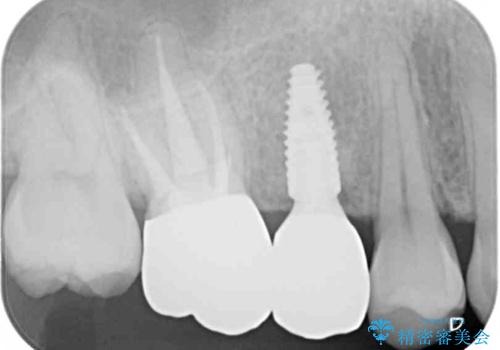

レントゲン撮影により、右上奥歯が折れていることが分かりました。

患者様自身も何となく違和感を覚えていたとのことで、インプラント補綴治療を行うこととしました。

歯列不正は比較的軽微であったので、インビザラインによる矯正治療とし、矯正治療中にタイミングを見て抜歯とインプラント埋入を行う予定としました。